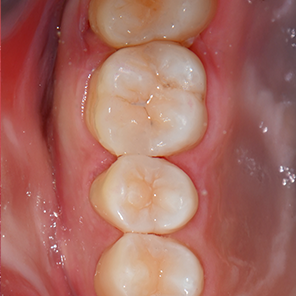

레진빌드업 치료 후

레진빌드업, 이러한 가치를 담아 진료합니다

보존 중심 접근 │ 자연치아의 건강한 부분을 가능한 보존하는 것을 목표로 진료 계획을 세웁니다.책임감 있는 진료 │ 상담부터 마무리까지, 모든 과정을 치과의사가 직접 세심하게 진행합니다.정밀 접착 과정 │ 치아와 재료가 긴밀하게 결합될 수 있도록 세심한 접착 단계를 거칩니다.자연스러운 조화 │ 주변 치아와의 색상이나 형태 등 전체적인 조화를 고려하여 수복을 진행합니다.